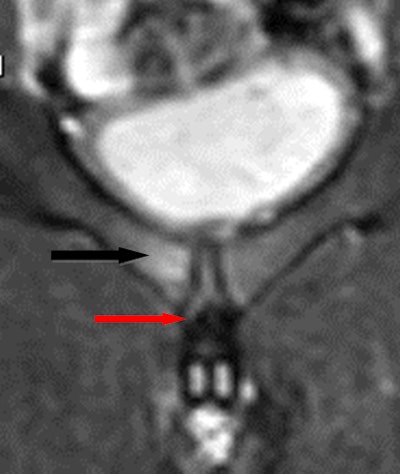

Gaelic football has similar injuries to football with groin, hamstring, and knee injuries being common. Besides, as Gaelic football allows catching of the ball, there are shoulder injuries similar to those in rugby. In the last decade or so, the change I have noticed most is the pattern of muscle injuries in the pelvis/thighs with fewer hamstring injuries and more groin injuries.

In my practice, we see a large amount of knee injuries (meniscal, cruciate, and medial collateral ligament) -- ankle injuries, predominantly ligaments, shoulders (dislocations with sequelae of same), hand injuries (particularly fractures in hurling and ulnar collateral ligament injuries), and groin pain (osteitis pubis, adductor/gracilis/rectus abdominis injuries, labral tears).

MRI is our test of choice for nearly all sports injuries, apart from obvious fractures and hand injuries. All knee, shoulder, hip, groin, and muscle injuries are evaluated with MRI. Shoulder and hip MR arthrography are reserved for those who have indeterminate noncontrast MRI for evaluation of labral and cartilage injuries or who have a high level of suspicion for these injuries from the outset. Ultrasound is often the first test for tendon injuries, such as Achilles, peroneal, and wrist tendons, with MRI reserved for more detailed analysis as necessary.